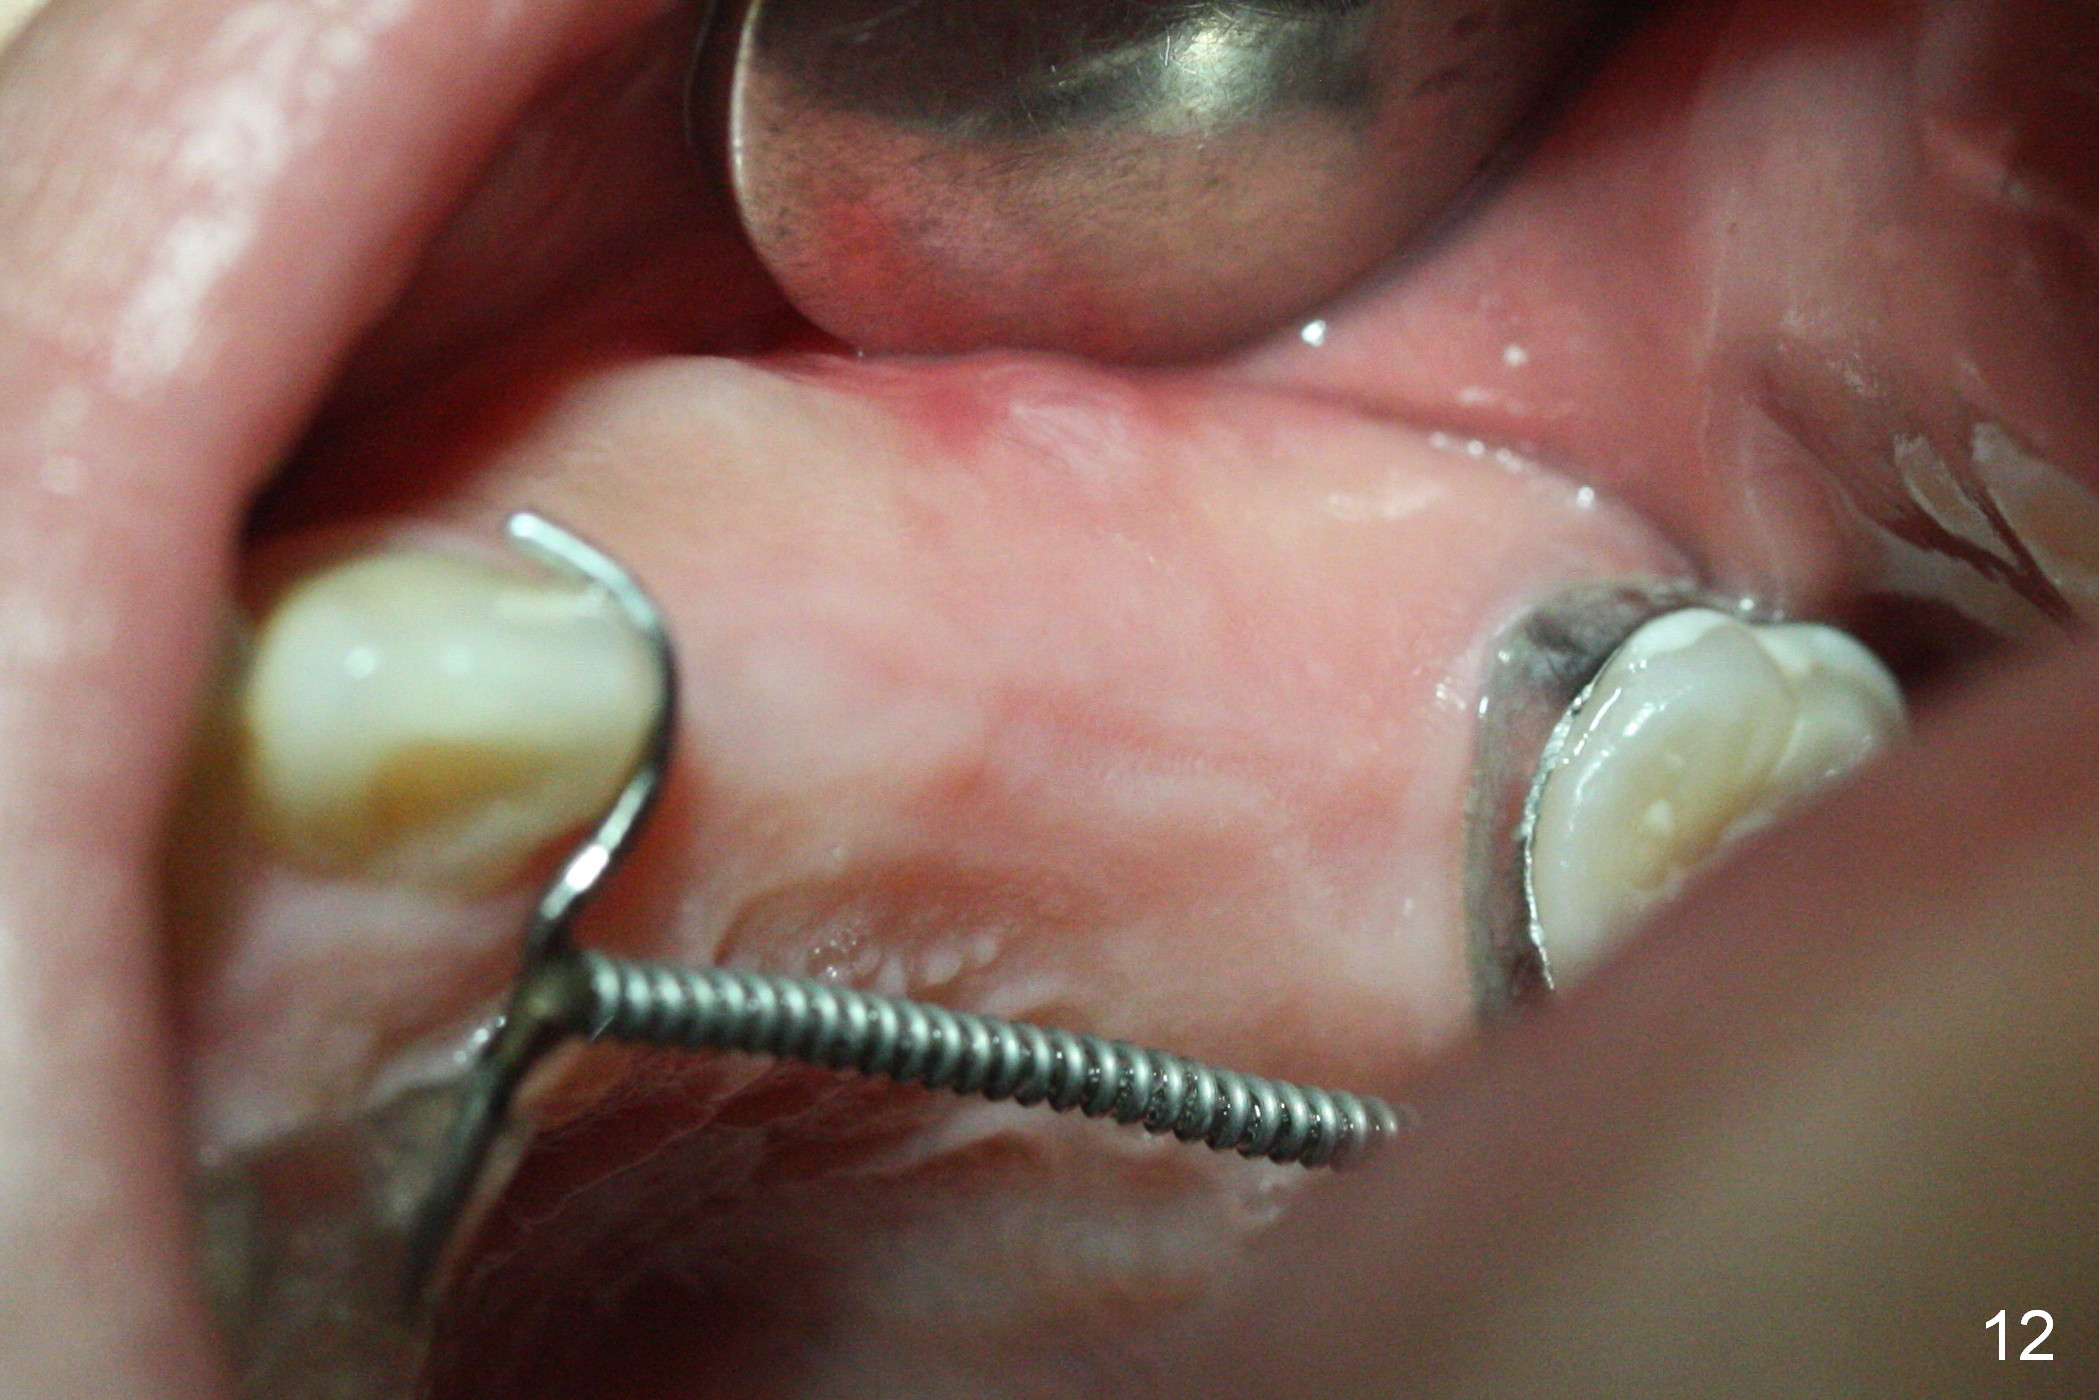

Nearly 2 months post regainer placement, UL6 appears to have been distalized (Fig.11 arrow), but UL4,5 have not erupted (Fig.12), while UL1,2 are displaced (Fig.13). Diode laser is used to expose the tooth buds, which are deeply seated (Fig.14). If they do not erupt soon, a mini implant should be placed for anchorage (Fig.10). Use several power chains to retract the anterior arm, while drill through the Nance appliance (high speed handpiece) for mini implant placement.